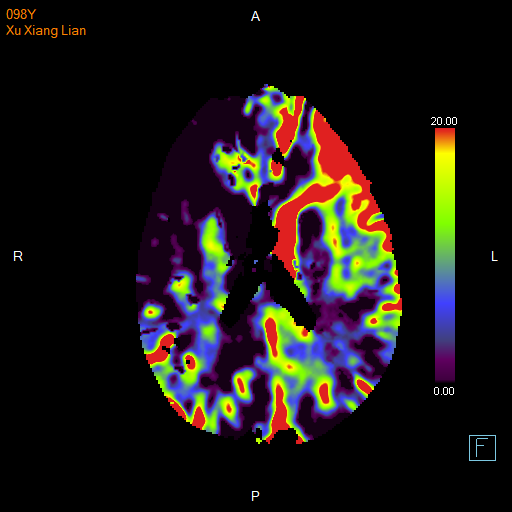

进一步的血管检查(CTA+CTP)发现了更严重的问题:王奶奶的左侧颈内动脉完全闭塞——这是脑梗中最凶险的类型之一,意味着大脑主要供血通道被切断,随时可能危及生命

颅脑 CTP